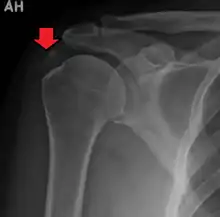

| A plain X ray of the shoulder showing calcific tendinitis | |

The calcific deposits are visible on X-ray as discrete lumps or cloudy areas. The deposits look cloudy on X-ray if they are in the process of reabsorption, and this is also when they cause the most pain. The deposits are crystalline when in their resting phase and like toothpaste in the reabsorptive phase. However, poor correlation exists between the appearance of a calcific deposit on plain X-rays and its consistency on needling. Ultrasound is also useful to depict calcific deposits and closely correlates with the stage of disease.[6]